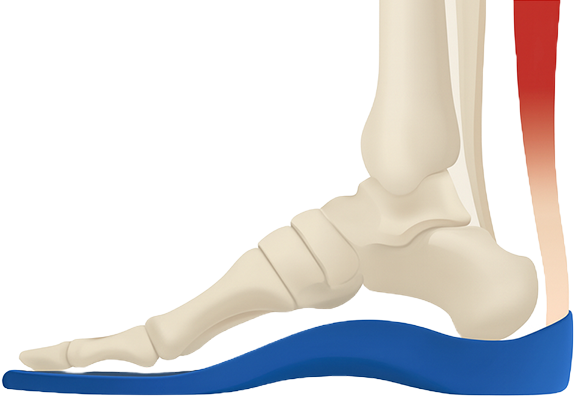

1:1 맞춤형 깔창 치료

염증이 생긴 아킬레스건염에 미치는 압력을 감소시키기 위해

뒷굽이 2~3cm 높은 치료용 1:1 맞춤형 깔창을 착용하여

하중을 분산시켜야 합니다.

발란스 깔창 치료

(일반용)

일상생활에서 착용하는데 권장하는 깔창으로 아치를 바쳐주어 통증을 최소화하고 발의 피로도를 낮춰주는 효과가 있습니다.

발, 발목 치료뿐 아니라 전신 교정 효과까지 기대해볼 수 있습니다.